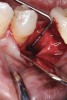

Fig 17. Bone graft was placed in the socket and a d-PTFE barrier was used to cover the graft. The bone graft material was placed beyond the alveolar housing to accommodate shrinkage of graft material and to facilitate attaining a wide alveolar ridge. The barrier was removed after 6 weeks.

Figure 17

Fig 22. Bone graft was placed in the socket and a d-PTFE barrier was used to cover the graft. The bone graft material was placed beyond the alveolar housing to accommodate shrinkage of graft material and to facilitate attaining a wide alveolar ridge. The barrier was removed after 5 weeks.

Figure 22